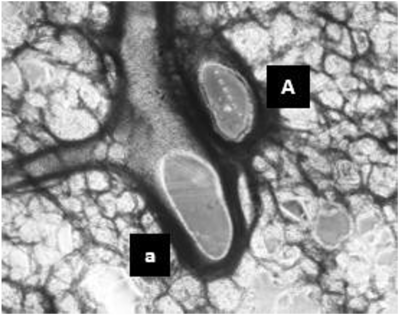

In Figure 2 (below), a thawed PCLS shows high viability and recapitulates both respiratory and vascular components. LEFT: Live/Dead staining (calcein AM and ethidium homodimer, respectively) demonstrate the high viability of thawed PCLS (imaged 2 days post-thaw, scale bar is 25µM). RIGHT: Brightfield image of a thawed PCLS with arteriole (a) and airway (A) labeled.

The lung represents a very complex intersection of the respiratory and vascular systems and resulting cytoarchitecture. AnaBios’ precision-cut lung slices accurately represent these components with high viability for successful downstream interrogation. PCLS samples show greater than 90% viability upon thaw and contain both respiratory and vascular components.